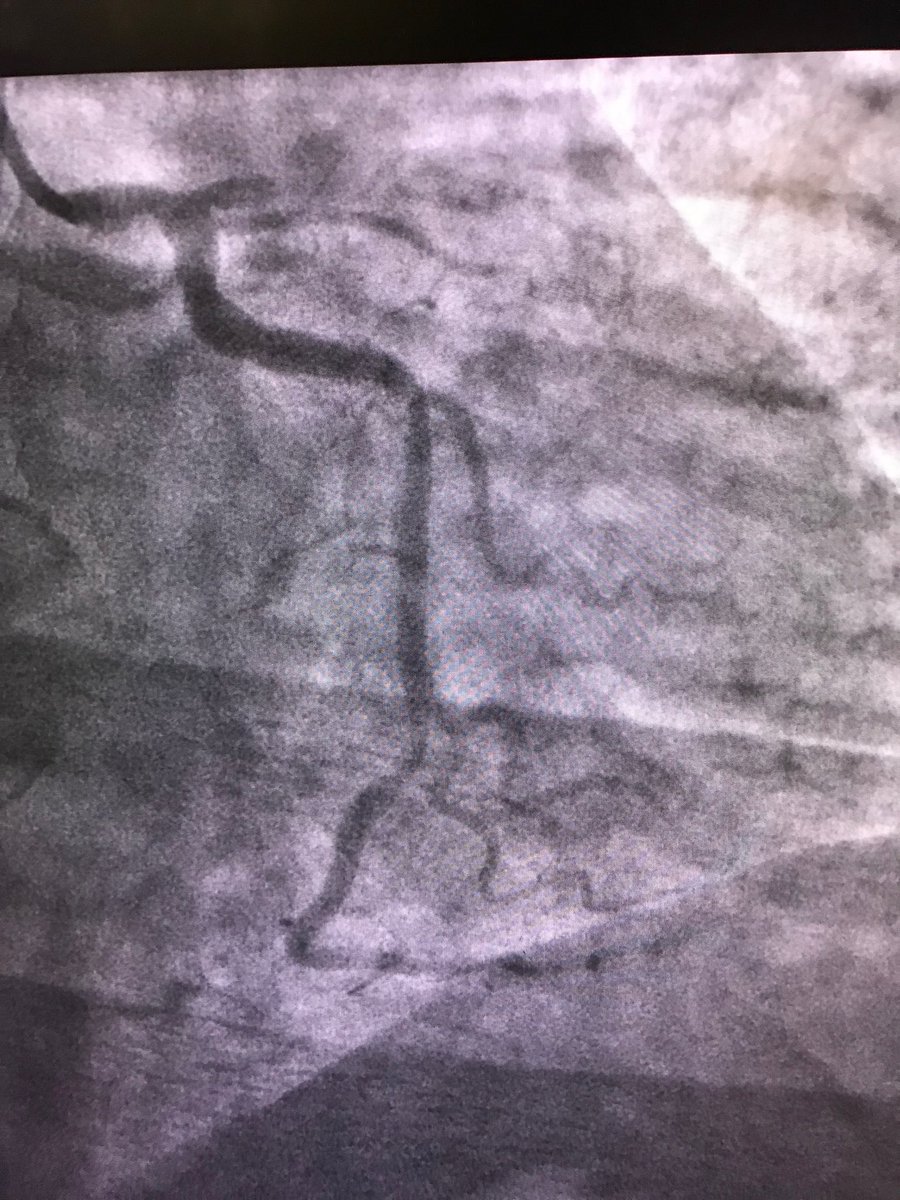

#protectedpci #RadialFirst #impella #safefemoral#ivus##unprotectedleftmainpci 61f#nstemi.6f45pinnacle inside 14f sheath .Successful #LMpci .left cfa occluded. bailout 014”grand slam/8x2balloon via rt radial. failed preclose ,safe balloon hemostasis while act240sec.#NoHematoma

istentem's tweet image. #protectedpci #RadialFirst #impella #safefemoral#ivus##unprotectedleftmainpci 61f#nstemi.6f45pinnacle inside 14f sheath .Successful #LMpci .left cfa occluded. bailout 014”grand slam/8x2balloon via rt radial. failed preclose ,safe balloon hemostasis while act240sec.#NoHematoma